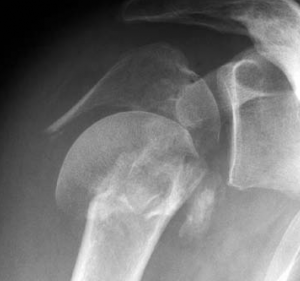

Oberarmkopfnekrose

Durch Medikamente (z.B. Cortison), übermäßigen Alkoholgenuss, als Unfallfolge oder andere noch nicht bekannte Ursachen kann es zu einer Minderdurchblutung des Oberarmkopfes kommen. Dies hat ein Absterben der Knochenzellen zur Folge, das zu einer Deformierung des Oberarmkopfes mit schmerzhafter Bewegungseinschränkung führt. Bei dieser Erkrankung reicht bei frühzeitigem Eingreifen eine Oberarmkopfprothese aus (Abb. 44a, b). Erst wenn durch die Inkongruenz der Gelenkflächen auch die Gelenkpfanne mitbetroffen ist, muss eine zusätzliche Pfannenkomponente implantiert werden.